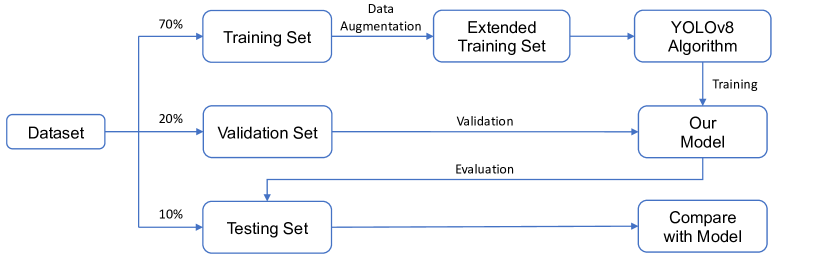

In this section, we introduce the process of the model training, validation and testing on the dataset, the architecture of YOLOv8 model, and the data augmentation technique employed during training. Figure 1 illustrates the flowchart depicting the model training process and performance evaluation. We randomly divide the 20,327 X-ray images of the GRAZPEDWRI-DX dataset into the training, validation, and test set, where the training set is expanded to 28,408 X-ray images by data augmentation from the original 14,204 X-ray images. We design our model according to YOLOv8 algorithm, and the architecture of YOLOv8 algorithm is shown in Figure 2.

To perform the experiments shown in Table 5 and Table 6, we divide the GRAZPEDWRI-DX dataset randomly into three sets: training set, validation set, and test set. The sizes of these sets are approximately 70%, 20%, and 10% of the original dataset, respectively. Specifically, our training set consists of 14,204 images (69.88%), our validation set consists of 4,094 images (20.14%), and our test set consists of 2,029 images (9.98%). The code for splitting the dataset can be found on our GitHub. We also provide csv files of training, validation and test data on our GitHub, but it should be noted that each split is random and therefore not reproducible.